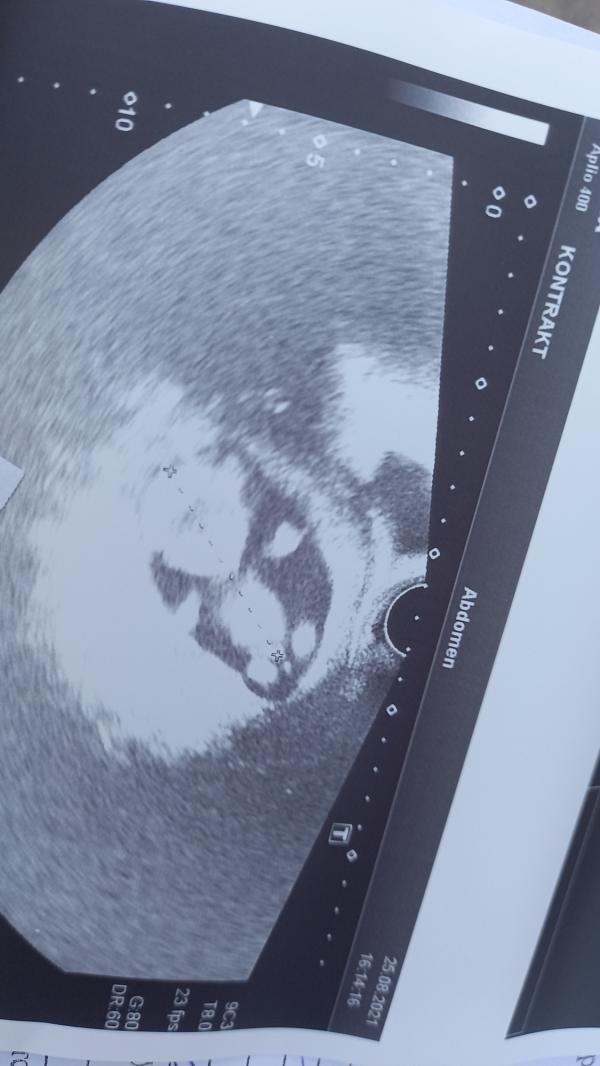

Потологий и пороков не наюлюдают, плод 14 недель

Сердцебиение прода 140 уд

Очень активный, машет ручками.

Вытягивается как акробат))

Сказали что бы готовились к мальчику, плечи широкие таз узенький. И вроде как писюн видать)))